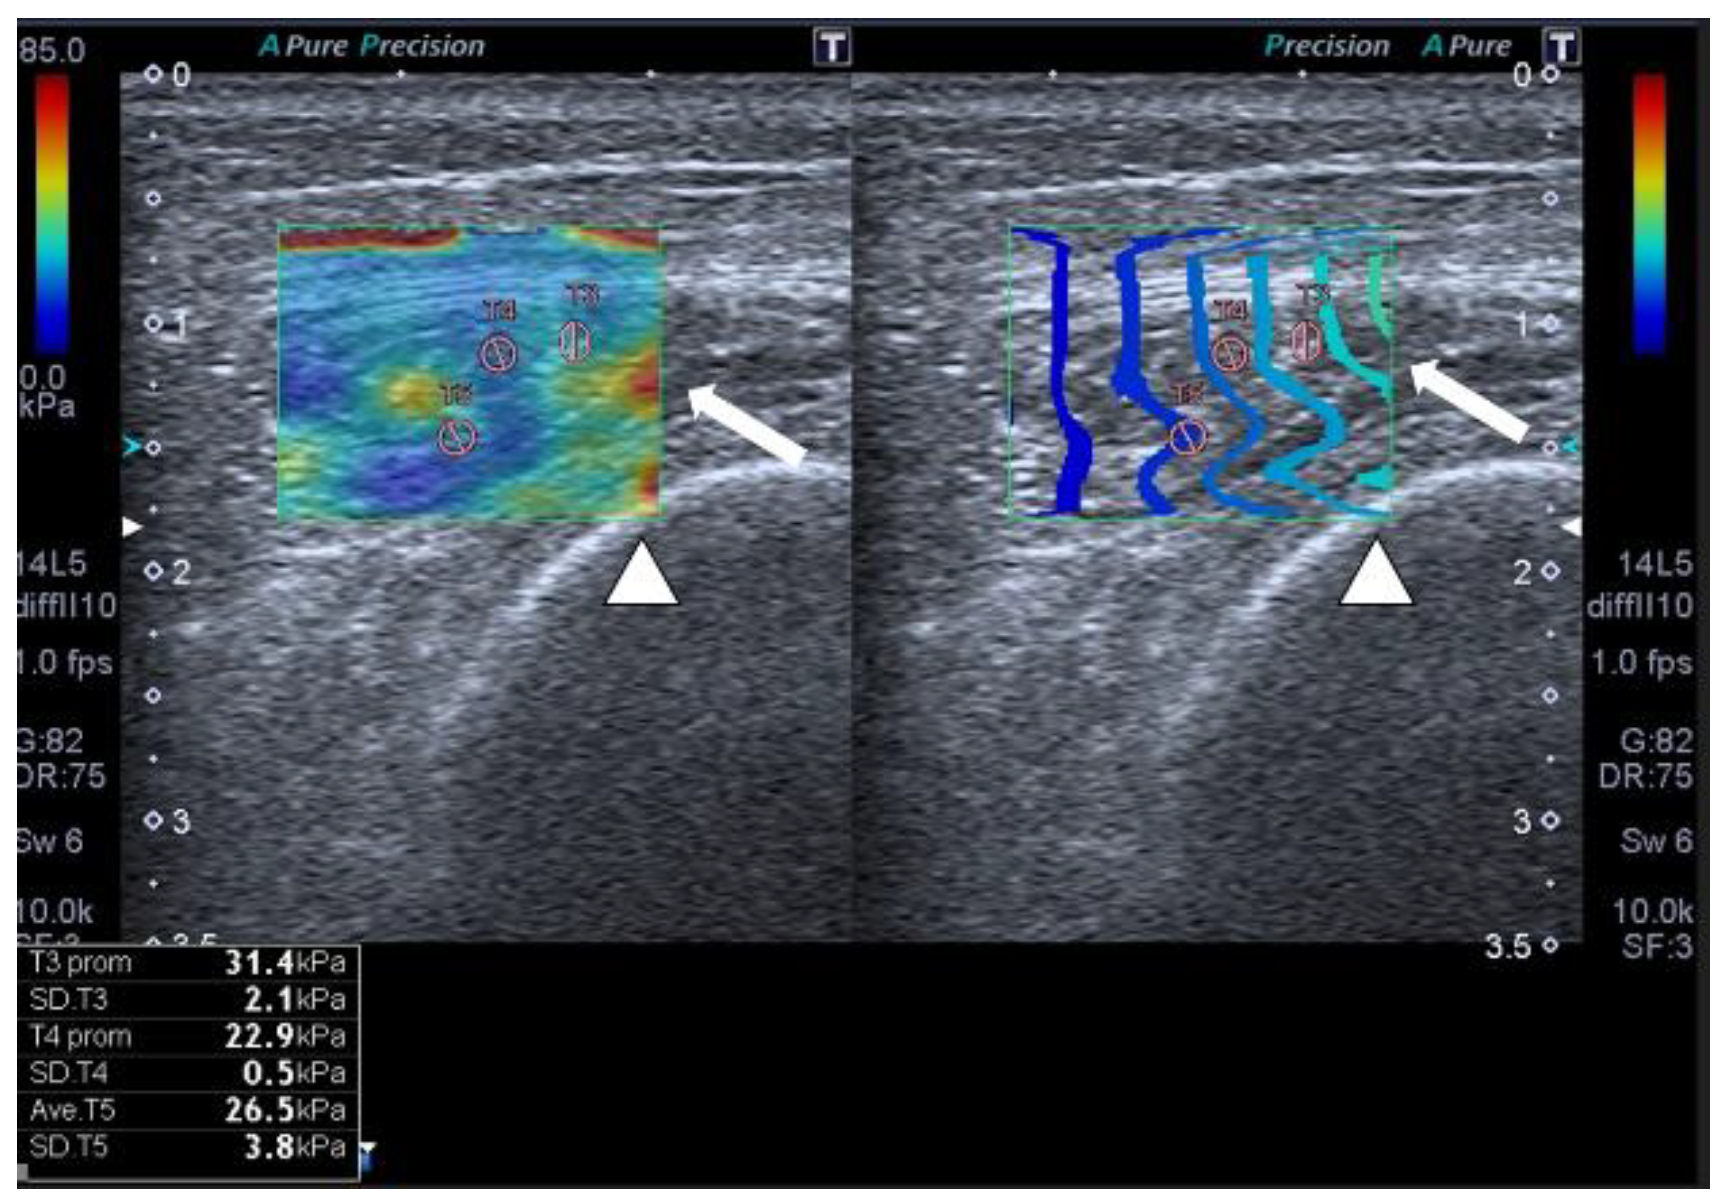

- Hernández-Socorro, C.R.; Saavedra, P.; López-Fernández, J.C.; Lübbe-Vazquez, F.; Ruiz-Santana, S. Novel high-quality sonographic methods to diagnose muscle wasting in long-stay critically ill patients: Shear wave elastography, superb microvascular imaging and contrast-enhanced ultrasound. Nutrients 2021, 13, 2224. [Google Scholar] [CrossRef]